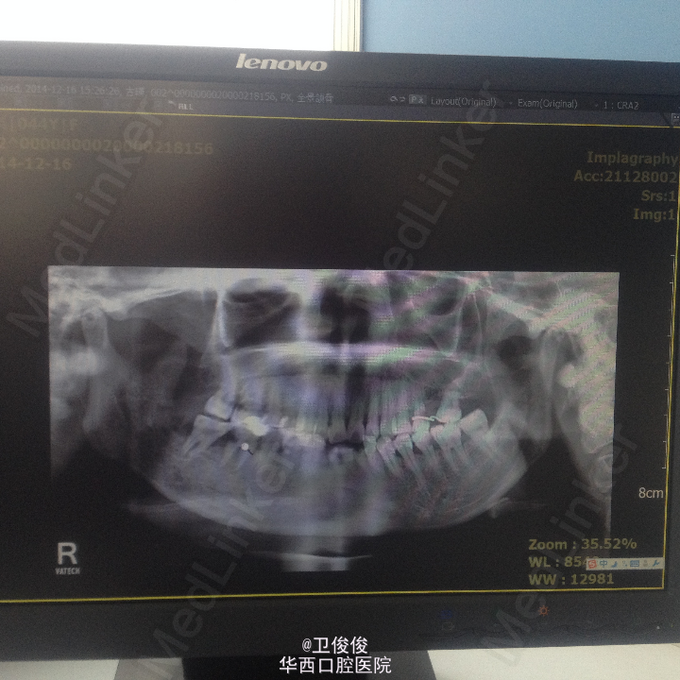

主诉:右侧颌下区有瘘口数周伴流脓 现病史:患者因鼻咽癌行局部放疗,放疗期间右侧后牙疼痛未治疗,数周前出现右侧颌下区皮肤肿胀,自行破溃,一直流脓,口服消炎药,效不佳

查体见:患者右颌下区见一瘘口,有脓血样液体流出, 全景结果是:右侧下颌升支及下颌角区可见骨质有吸收,47可见远中有龋坏。

诊断:放射性骨髓炎 处理:长期换药,待死骨分离